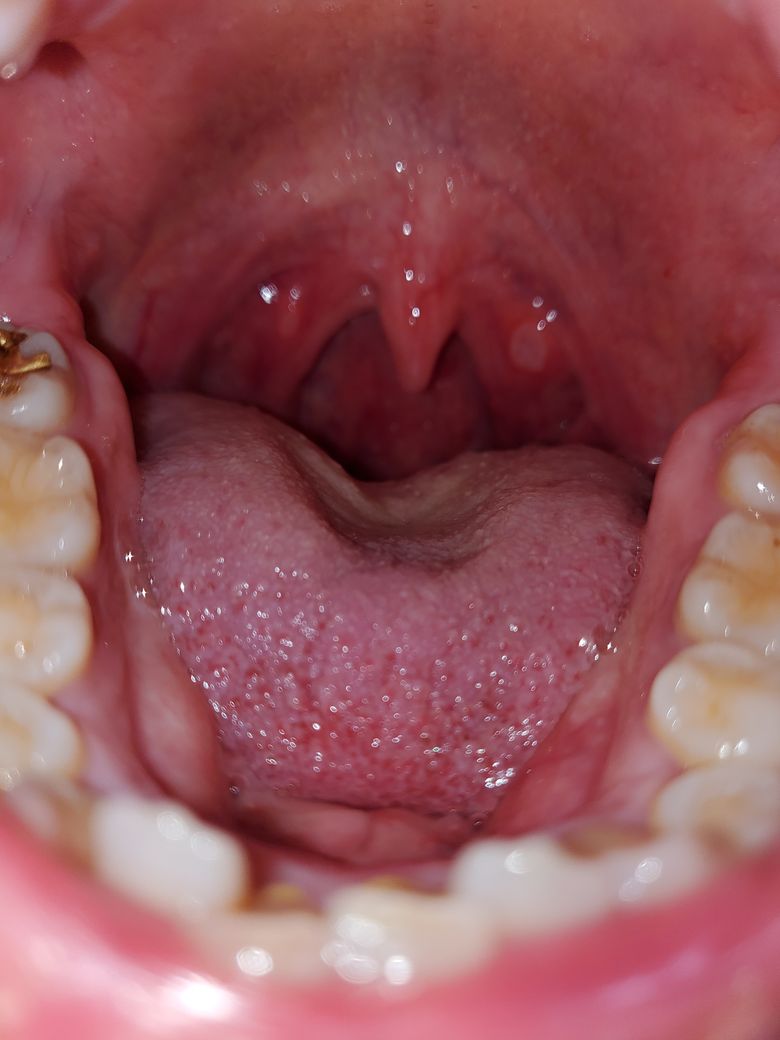

항생제를 5일치 먹고 일주일이 지났는데 더 심해졌어요.ㅜㅜ 병원에 안가도 나아질까요?

물만먹어도 너무아프고 잠도 설치고있어서 괴롭네요

목 안의 상태만 봐서는 편도가 부어 있는 것도 아니라서 항생제 복용이 필요한 것 같지는 않습니다. 인후에 궤양이 약간 있어서 구내염 소견이라고 판단되는데 구강 연고를 바르면서 증상 조절을 해 보셔도 괜찮을 것 같아요.